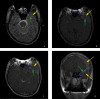

We report the case of 22-year-old man with nontraumatic intracystic hemorrhage into a middle cranial fossa arachnoid cyst associated with a contiguous subacute subdural hematoma. Arachnoid cysts are benign intra-arachnoidal fluid collections frequently detected incidentally during neuroimaging. Rare complications of arachnoid cysts such as intracystic hemorrhage or subdural hematomas and subdural hygromas typically occur after head trauma. Our review of the literature identified fewer than 30 cases of arachnoid cysts with complicating intracystic hemorrhage and ipsilateral subdural hematomas.